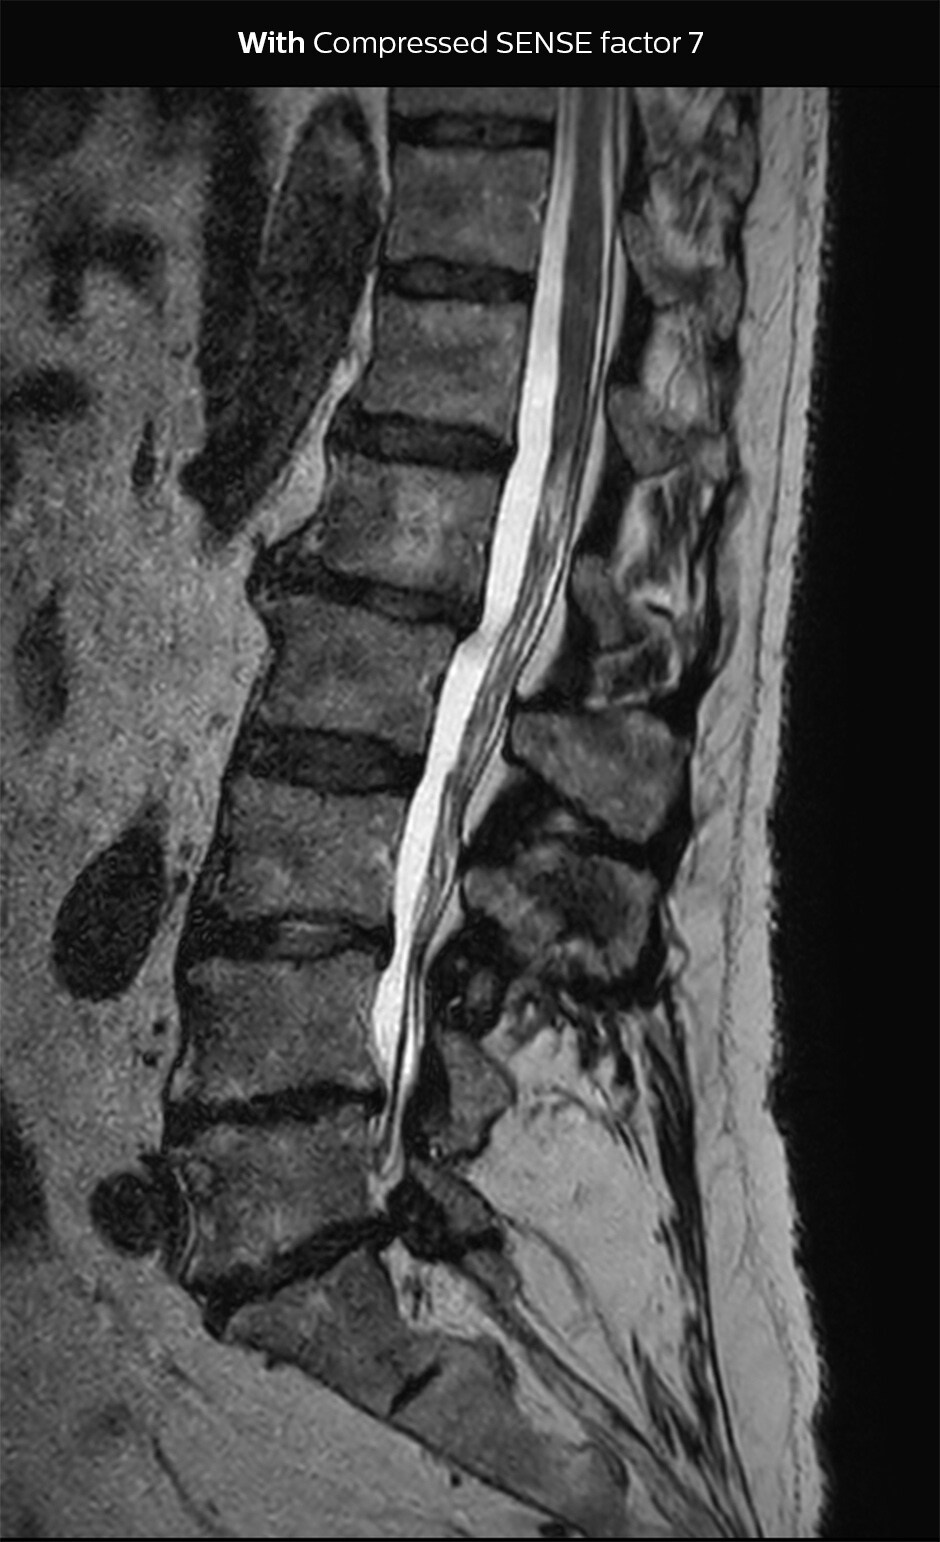

“Our aim for the spine is to use Compressed SENSE to help us make the switch to using 3D SpineVIEW. In lumbar spine, for example, we can reduce scan time for 3D T2W SpineVIEW by 27% to 4:46 minutes, voxel size 0.8 x 0.8 x 1 mm."

In this example Compressed SENSE has a 26% shorter scan time and improved spatial resolution simultaneously.

3D T2 SpineVIEW, scan time 6:29 min, voxel size 1 x 1 x 1.4 mm

3D T2 SpineVIEW, scan time: 4:46 min, voxel size 0.8 x 0.8 x 1 mm

In some cases, Dr. Sartoretti also sees the benefit of keeping the acquisition time the same, and increase the amount of detail in images. “In nerve imaging, for example of plexus and in peripheral neurography, more detail is helpful to see the tiny nerves. We also like to add Compressed SENSE to the 3D T1 Black Blood sequence, for obtaining higher resolution when looking at the detailed anatomy of vessel walls and to visualize pathology of these tiny vessels in the brain.” The lumbar spine example above also illustrates an improvement of spatial resolution with use of Compressed SENSE.